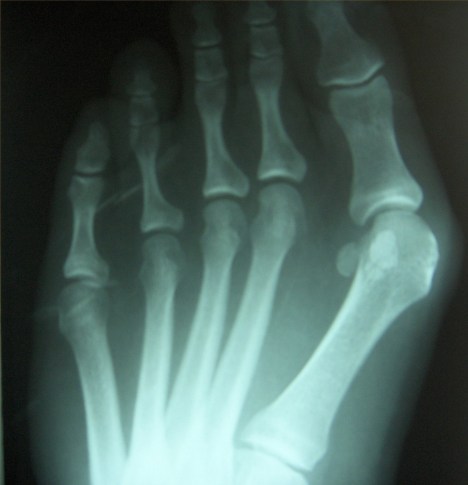

That x-ray is actually .. 7? years old :) There are multiple stress fractures, bone spurs, and a general all-round deformity. Feet are supposed to look like this: ||||| .. mine look like this: (///> !

And the remedy is either robo-feet (which my then-current doctor was afraid of doing because it was hella mad complicated and would require a total rebuild), or amputation. That being said, my feet are a LOT better than they were 8 years ago .. I would frequently be completely unable to walk due to pain, whereas now I don’t hurt unless I’ve been walking around London non-stop for four days. :)

Wow! Pretty severe bunion on that foot. What’s the remedy? Orthotics? Corrective surgery? Amputation?